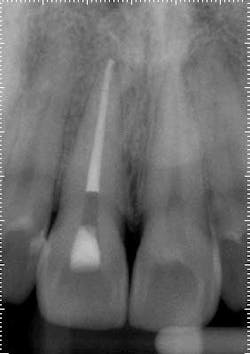

Treatment options: Root canal treatment No. 8, no treatment, or extraction. The patient was certain tooth No. 3 was the culprit, and No. 8 had no restorative or trauma history. As a result, waiting for symptoms to localize was a consideration. However, the patient experienced significant relief following administration of local anesthetic around tooth No. 8, and a root canal was completed.Posterior right

Treatment: Upon access, a necrotic pulp was identified. The dentin triangle was removed with a series of Gates-Glidden burs. Copious irrigation was completed with sodium hypochlorite. The canal was instrumented with stainless steel hand files and rotary ProFile series 29, both 0.04 and 0.06 taper. The canal was filled with a warm vertical downpack and thermoplasticized gutta-percha backfill. To maximize esthetics, the space was underfilled to the level of the crestal bone to prevent staining the chamber.